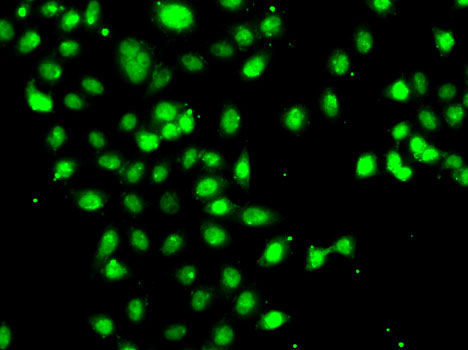

Immunofluorescence analysis of A-549 cells using CEBPG .